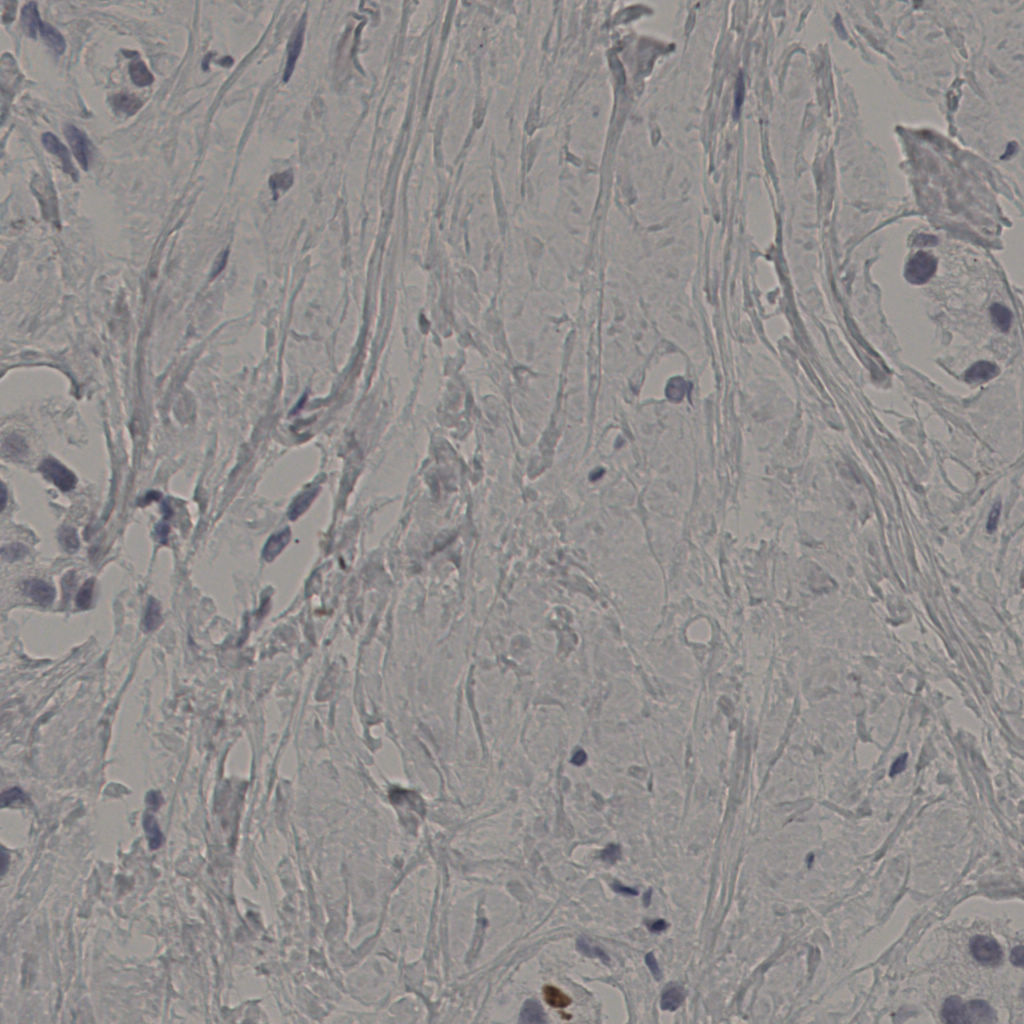

5.31%

Ki67 指数

阴 19502

阳 1093

切片统计

总切片

2970

有效

554

已标记

554

有效率

19%